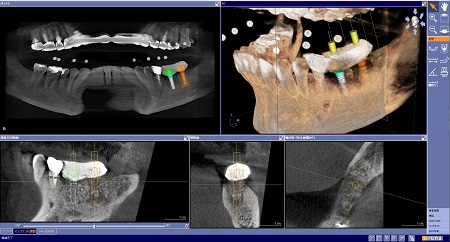

3D画像構築ソフトウェア GALILEOS Implant

CTを撮影したあと、データを画像として構築するため使用されるのが3Dソフトウェア GALILEOS Implantです。特徴として、神経管や骨がビジュアル化されて確認でき、患者さんの顎の骨の中の状態を解剖学的に知ることができます。

特にインプラント治療では、SICATサージカルガイドを作成してプランニングすることで、より安全な手術(ガイドサージェリー)を行うことができます。

3Dカメラを使うセレックシステムとCTを3D解析できるガリレオスのデータを融合して、コンピューター上でインプラント埋入から被せ物のセットまでシミュレーションできる技術です。これによりインプラントの最終的な形が予測できる上、神経や血管を傷付けないか、加えて骨を足すなどの治療が必要か等もわかります。

CTによるレントゲン撮影